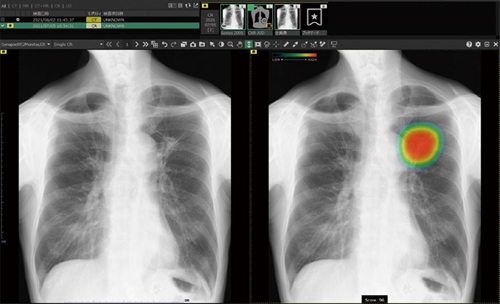

“ヒートマップ+スコア表示”で、説明がより分かりやすく

AI解析後は、疑わしい部位の確信度(0~100)に応じて色分けするヒートマップが表示され、スコアも確認できます。

これにより、診察室で画像をお見せしながら

「どこが、なぜ気になるのか」を、より視覚的に分かりやすくご説明できるようになります。

患者さまにとっても、検査結果の納得感が高まりやすいのが大きなメリットです。